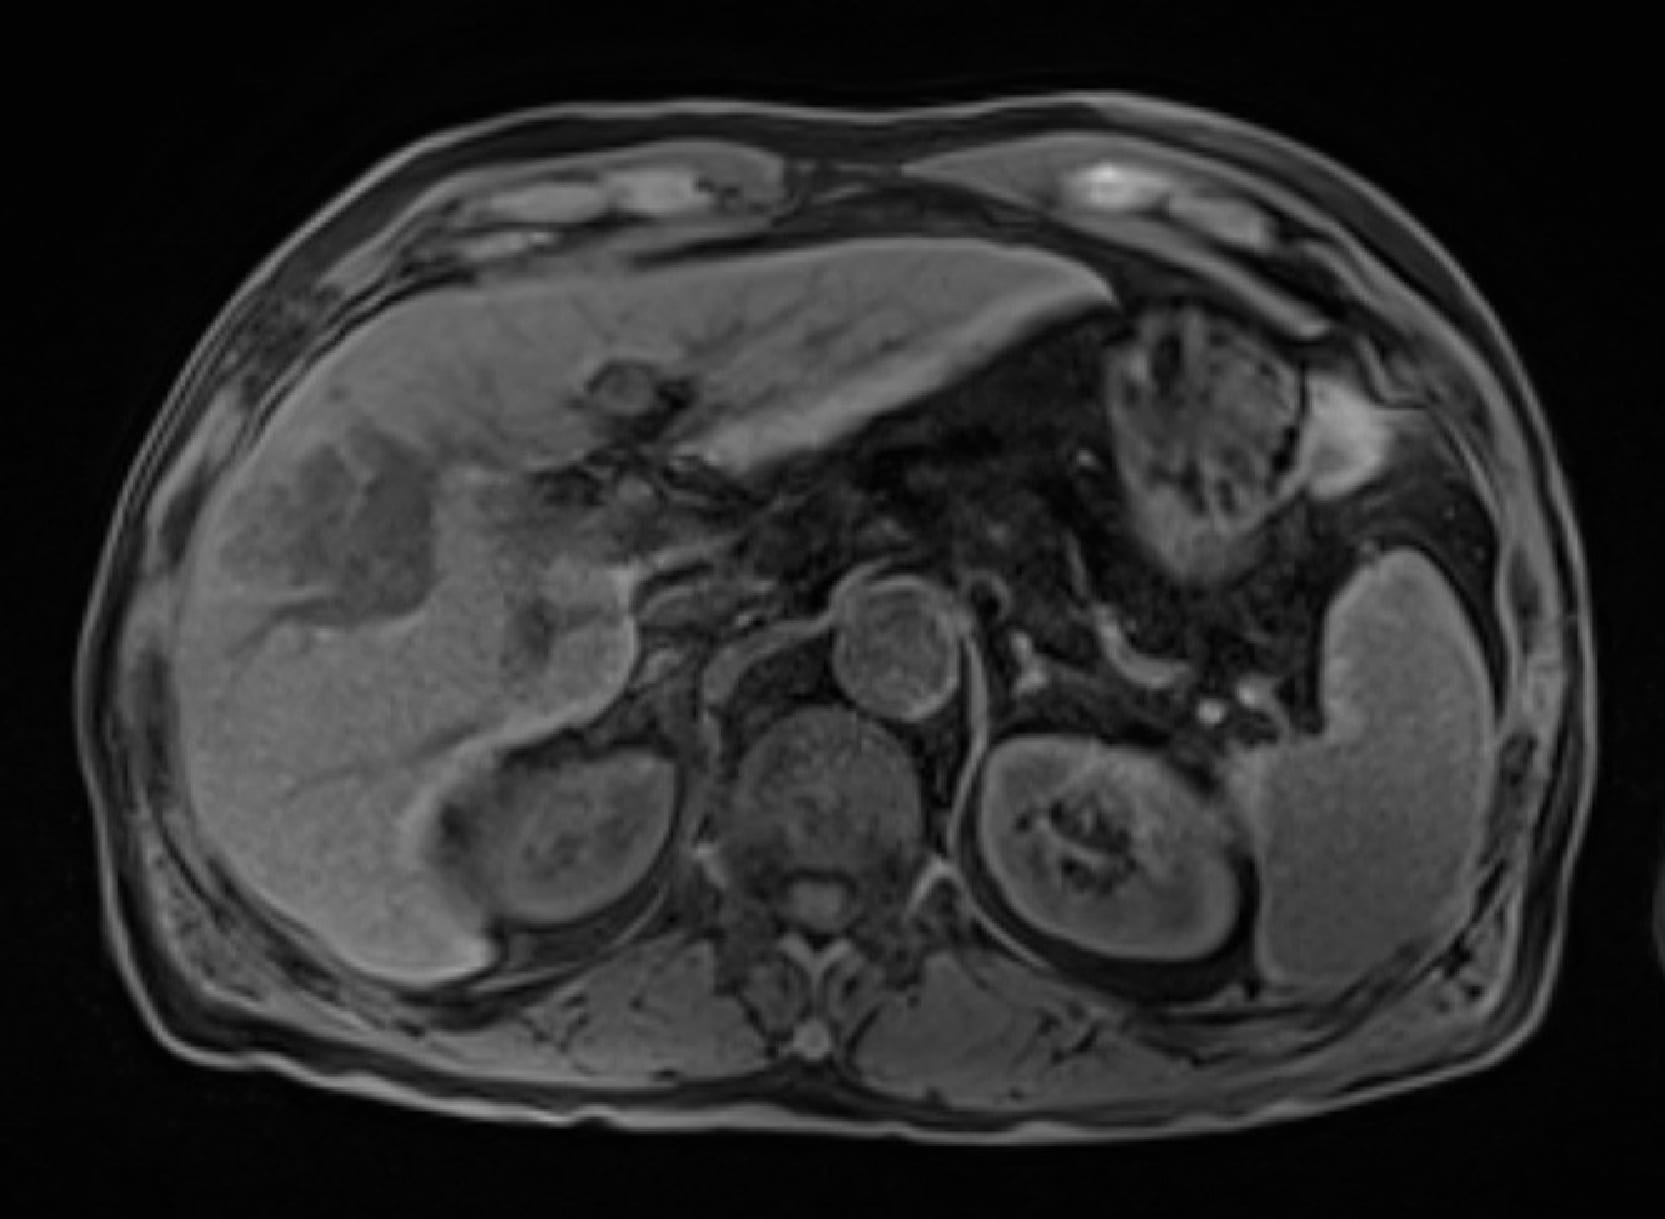

Fig. 1. Pretreatment simple EOB-MRI

A mass lesion in the anterior segment of the right lobe of the liver was slightly dark staining.

Fig. 2. Pretreatment early phase

The mass lesion in the anterior segment of the right lobe of the liver showed wash-out, with the branched part corresponding to the route of the portal vein, and the possibility of it being a portal vein tumor embolism was considered.